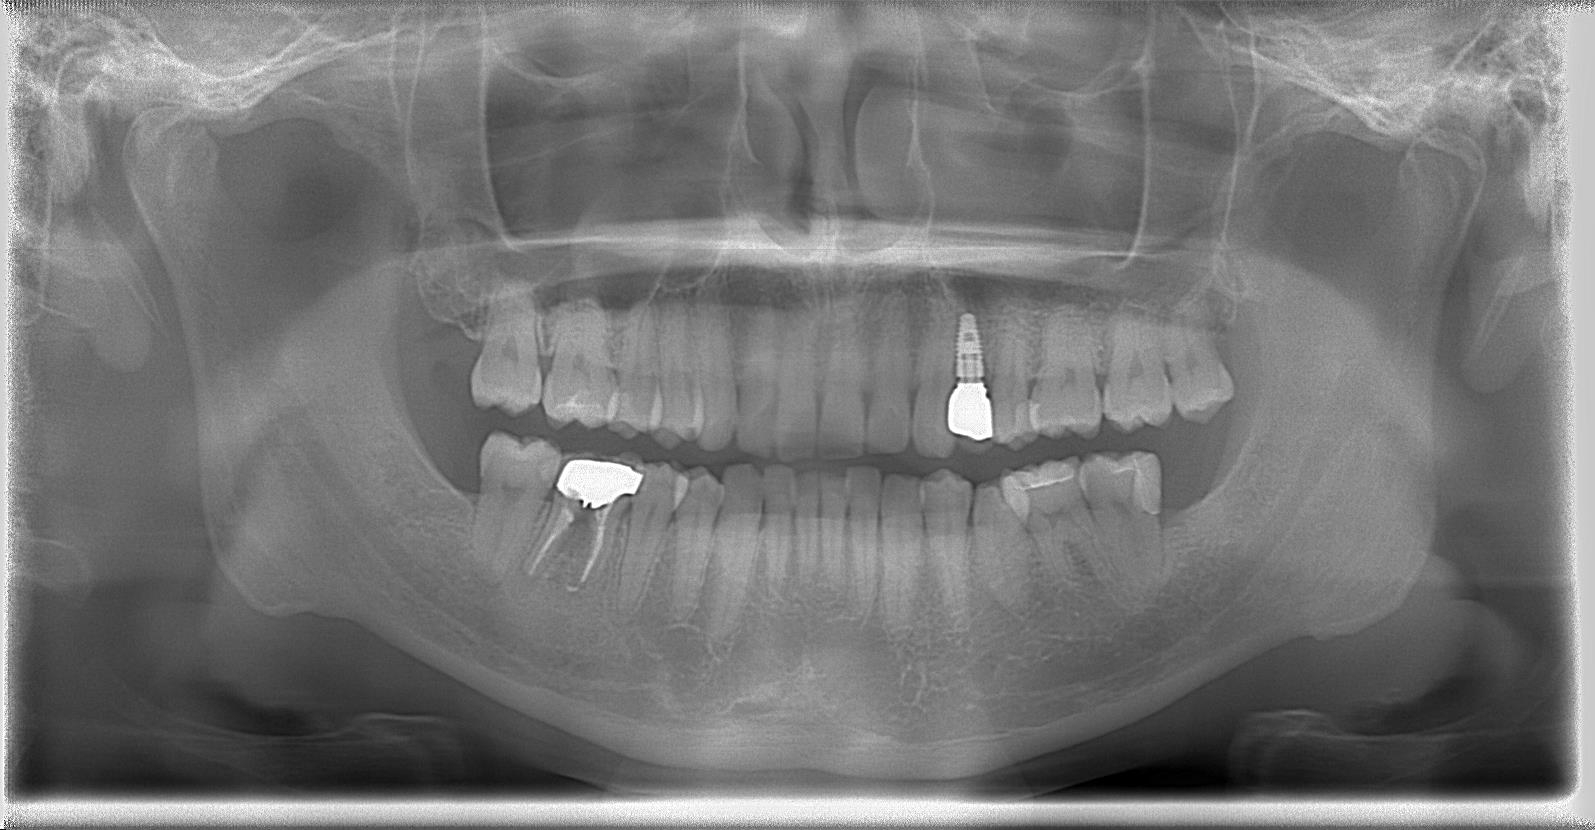

術後パノラマレントゲン写真